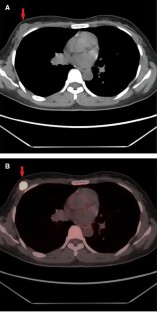

Fig. 1